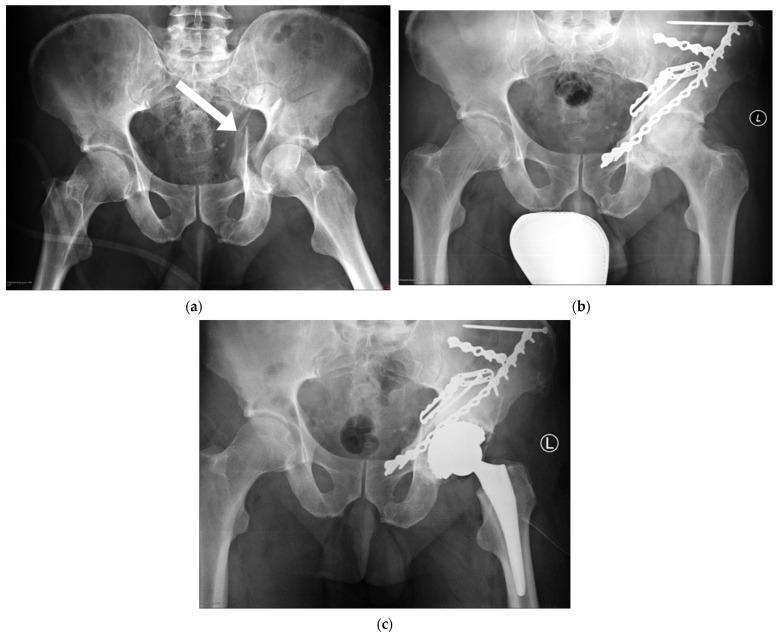

髋臼骨折切开复位内固定(ORIF)术后患者的治疗结果的影像学和功能评估。

Radiological and Functional Assessment of Treatment Outcomes in Patients after Open Reduction with Internal Fixation (ORIF) of Acetabular Fractures.

(1) Fracture of the pelvis usually happens in young men and results from high-energy trauma. It generates high social and economic costs and results in further health problems. It is therefore important to assess long-term treatment results. (2) The study (NCT04902209) involved 31 patients (mean age 43.6 ± 14.8 years). We conducted fixation assessment on the basis of radiographs and CT scans and functional assessment based on functional scales. (3) We observed more degenerative changes in the less precise reconstruction of the acetabulum ( = 0.075). We did not find statistically significant relationships between the area of surgical approach, the gravity of fracture, and the development of degenerative changes. We did not find statistically significant relationships between patients' functional states and the type of surgical approach or the complexity of the fracture. We found a positive correlation between the time of surgical treatment and patients' functional state ( = 0.04). Patients whose joint surfaces were reconstructed anatomically had significantly higher scores in functional scales (HHS = 0.05, Merle = 0.03). (4) Patients after surgical fixation of the acetabulum have low functional abilities. The quality of reconstruction of the loaded surface as well as the length of time post-surgery seems to be essential for the patients' functional state.

摘要